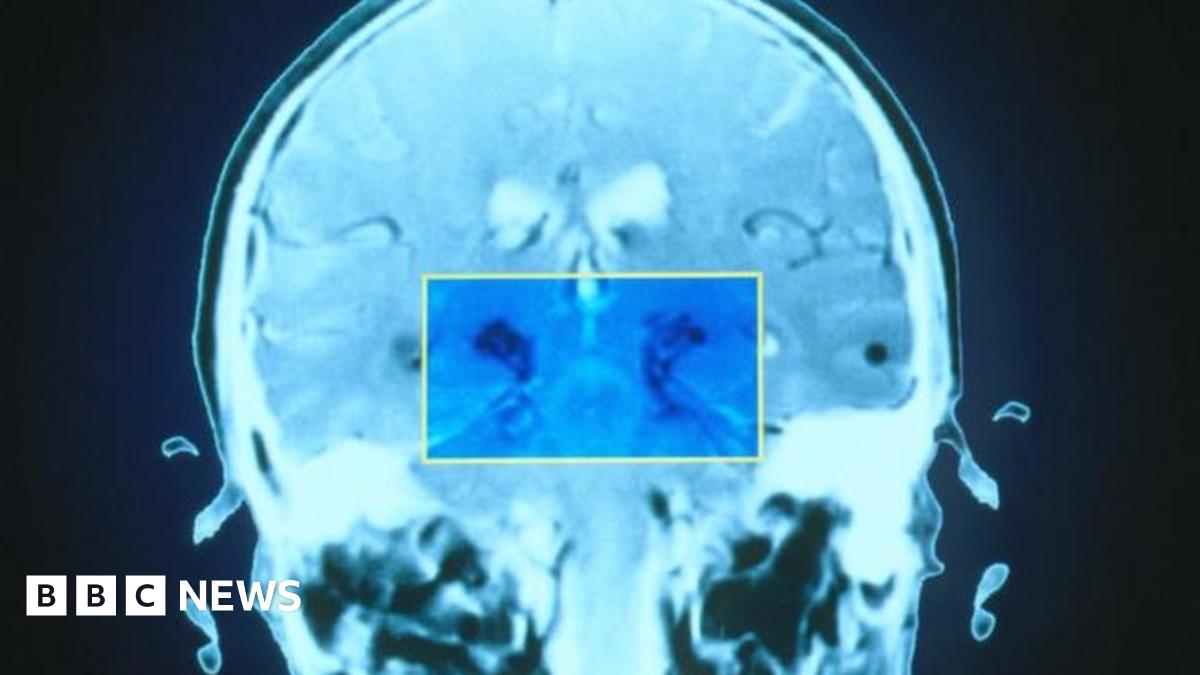

The technology works partly by tracking the motion of vocal cords

The system "learns" to detect differences in voice patterns.